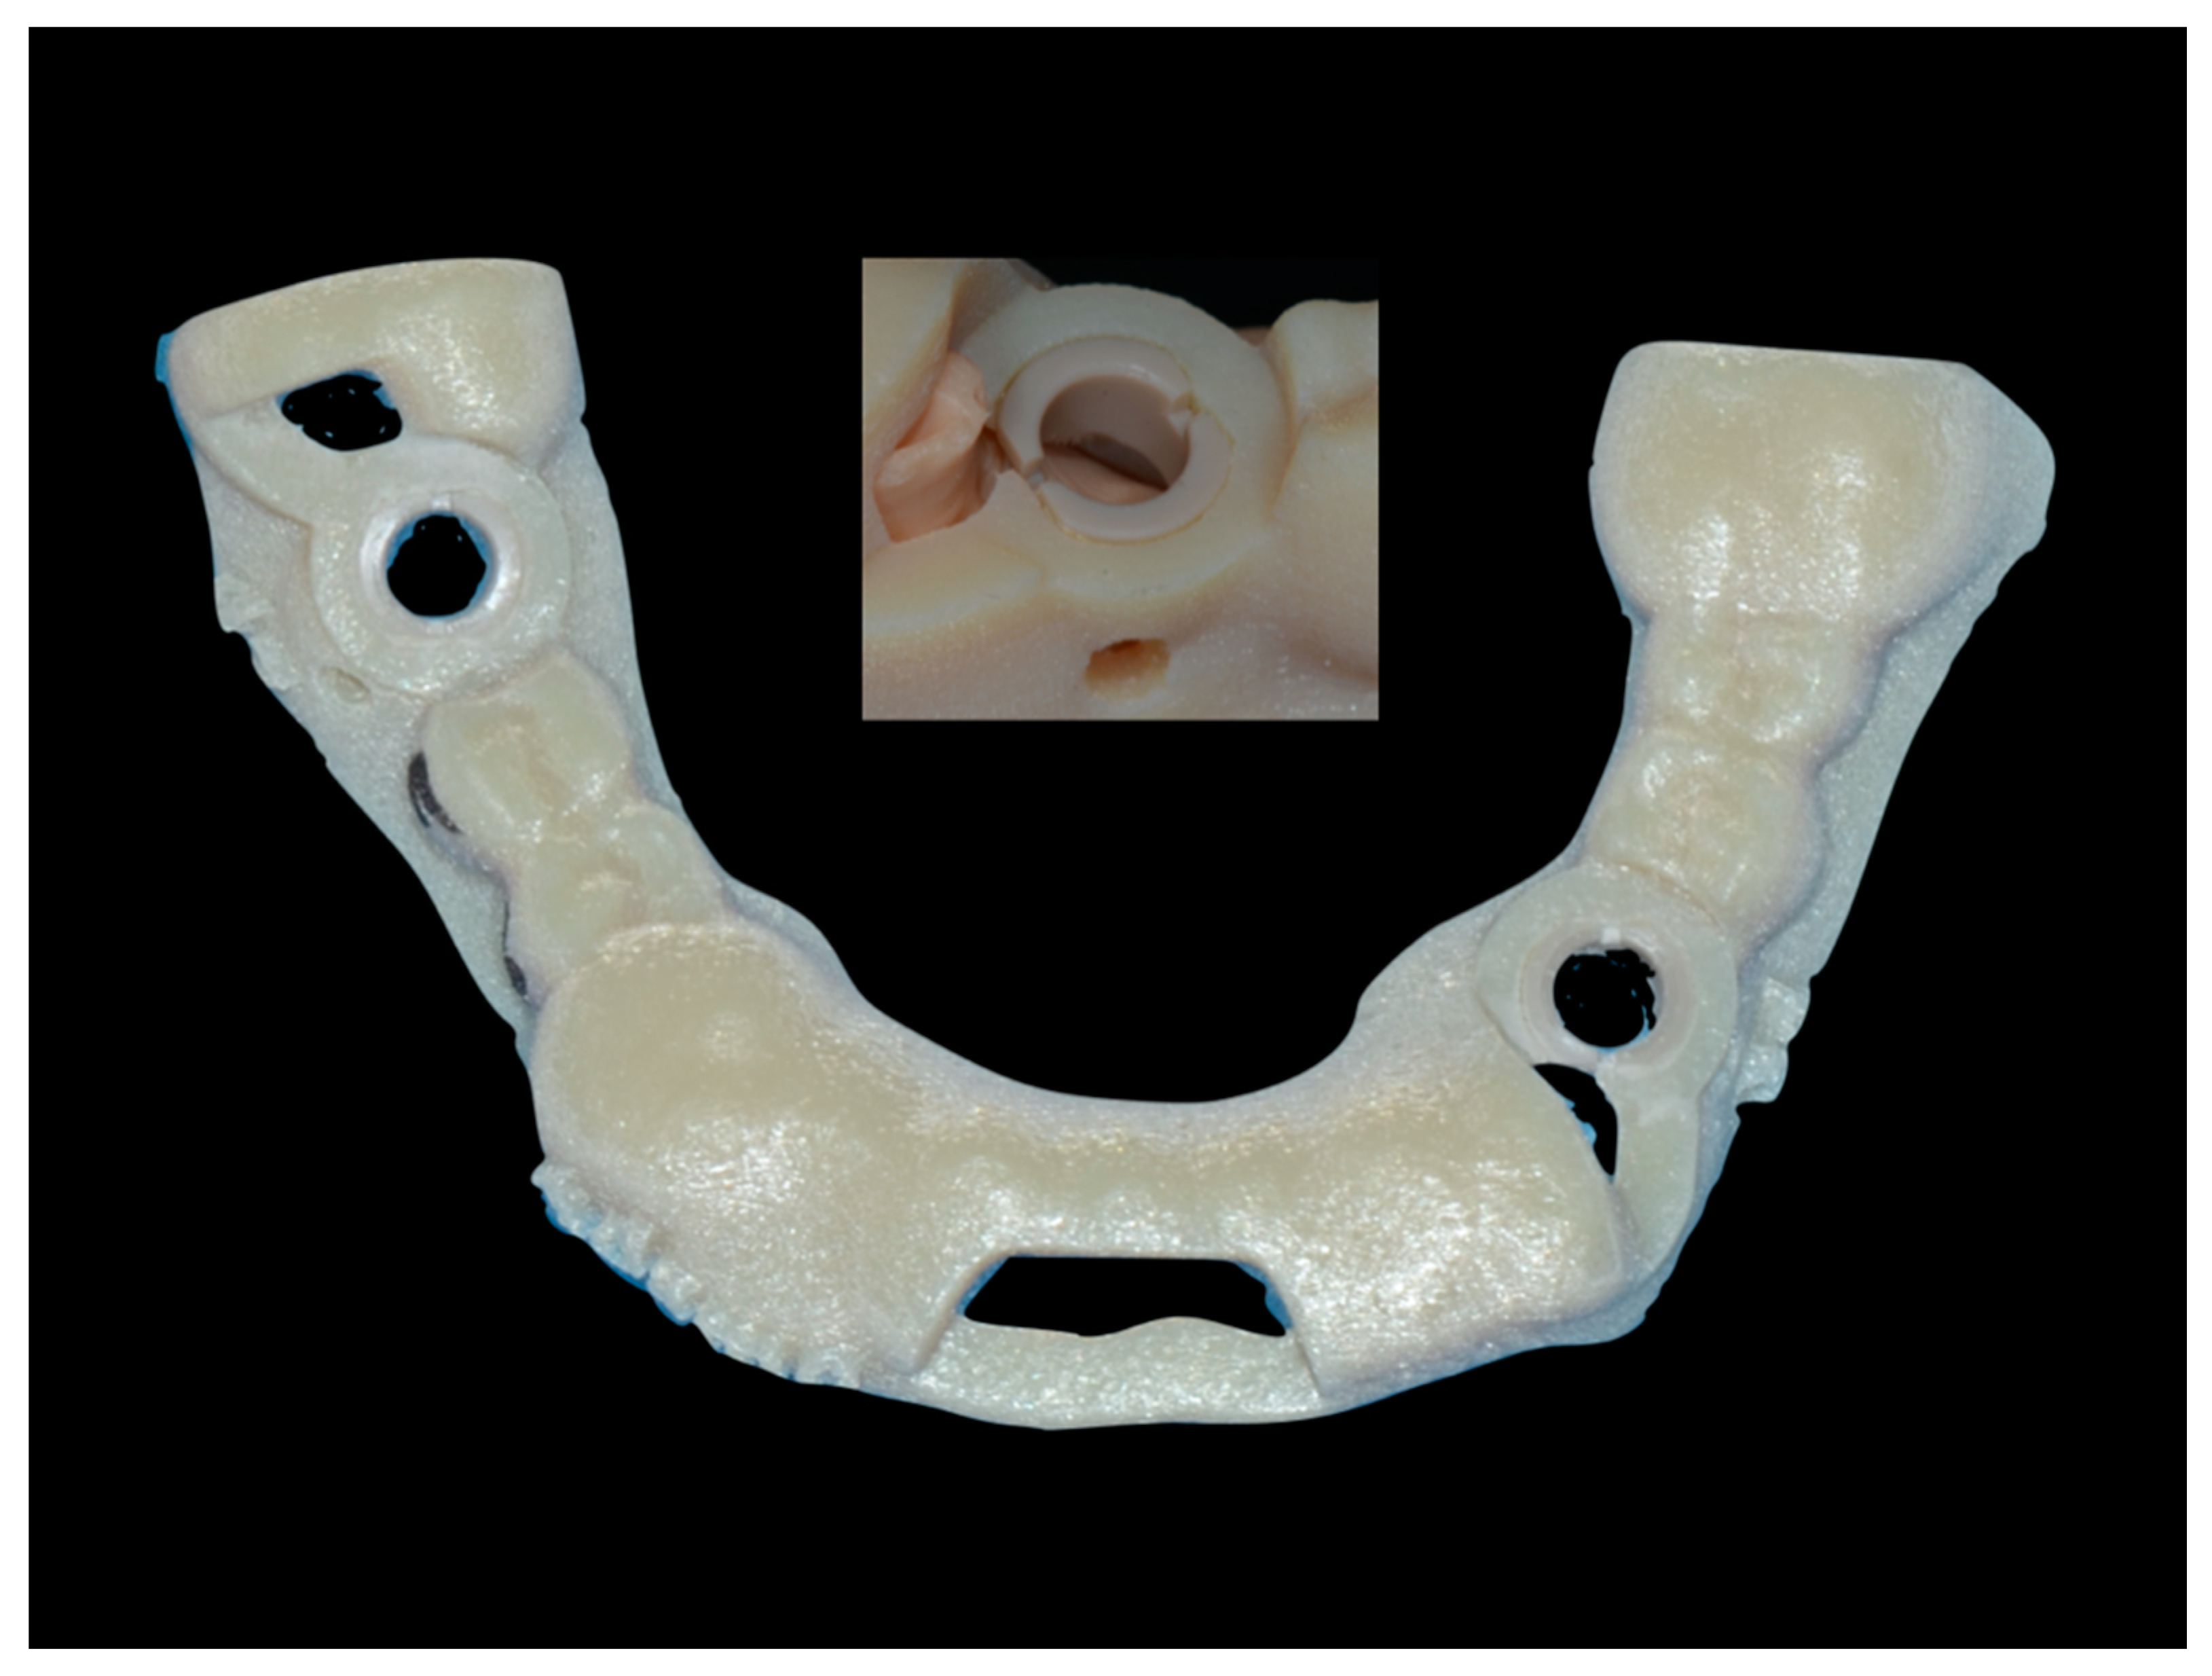

2.1. Static Computer Aided Implantology Workflow (SG)